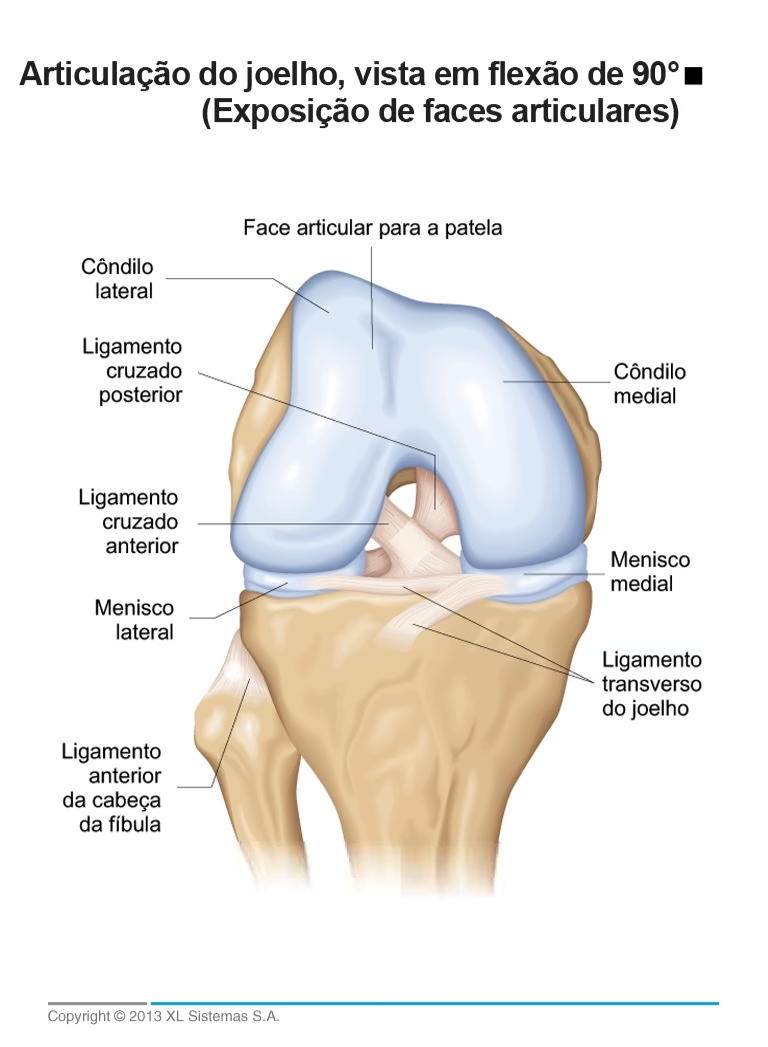

Los ligamentos de la rodilla (cruzado anterior, cruzado posterior, colateral medial, colateral lateral) son cruciales para la estabilidad. Las lesiones del ligamento cruzado anterior (LCA) son particularmente comunes en deportes que implican giros, saltos y cambios rápidos de dirección. La reconstrucción del LCA es una de las cirugías deportivas más frecuentes. En este procedimiento, el ligamento dañado se reemplaza con un injerto de tejido, que puede ser autoinjerto (del propio paciente, como tendón rotuliano o isquiotibiales) o aloinjerto (de un donante). La cirugía se realiza generalmente por artroscopia, minimizando la invasión y el tiempo de recuperación inicial, aunque la rehabilitación completa puede llevar varios meses.

Los meniscos son dos estructuras de cartílago en forma de C que actúan como amortiguadores y estabilizadores de la rodilla. Los desgarros meniscales son lesiones muy comunes, especialmente en deportes o con el envejecimiento. El tratamiento de estas lesiones se realiza con frecuencia mediante artroscopia, una técnica mínimamente invasiva que utiliza una pequeña cámara y herramientas finas introducidas a través de pequeñas incisiones. Las opciones quirúrgicas incluyen: